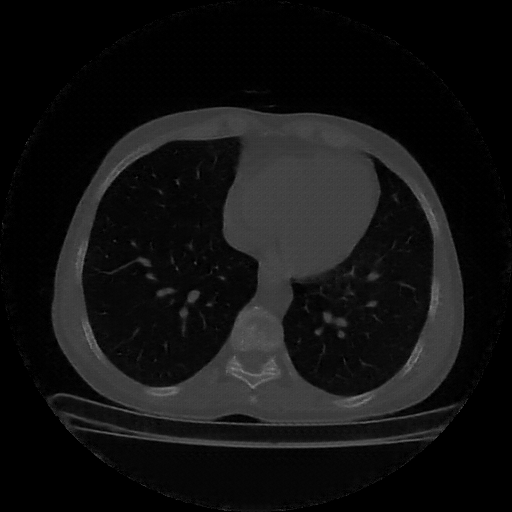

Reconstructed NATIVE CT scan (cycle consistency)

Full window (WL 1023.5, WW 4095 β†’ Low βˆ’1024, High +3071)

Lung window (WL -600, WW 1500 β†’ Low βˆ’1350, High +150)

Mediastinum window (WL 40, WW 400 β†’ Low βˆ’160, High +240)